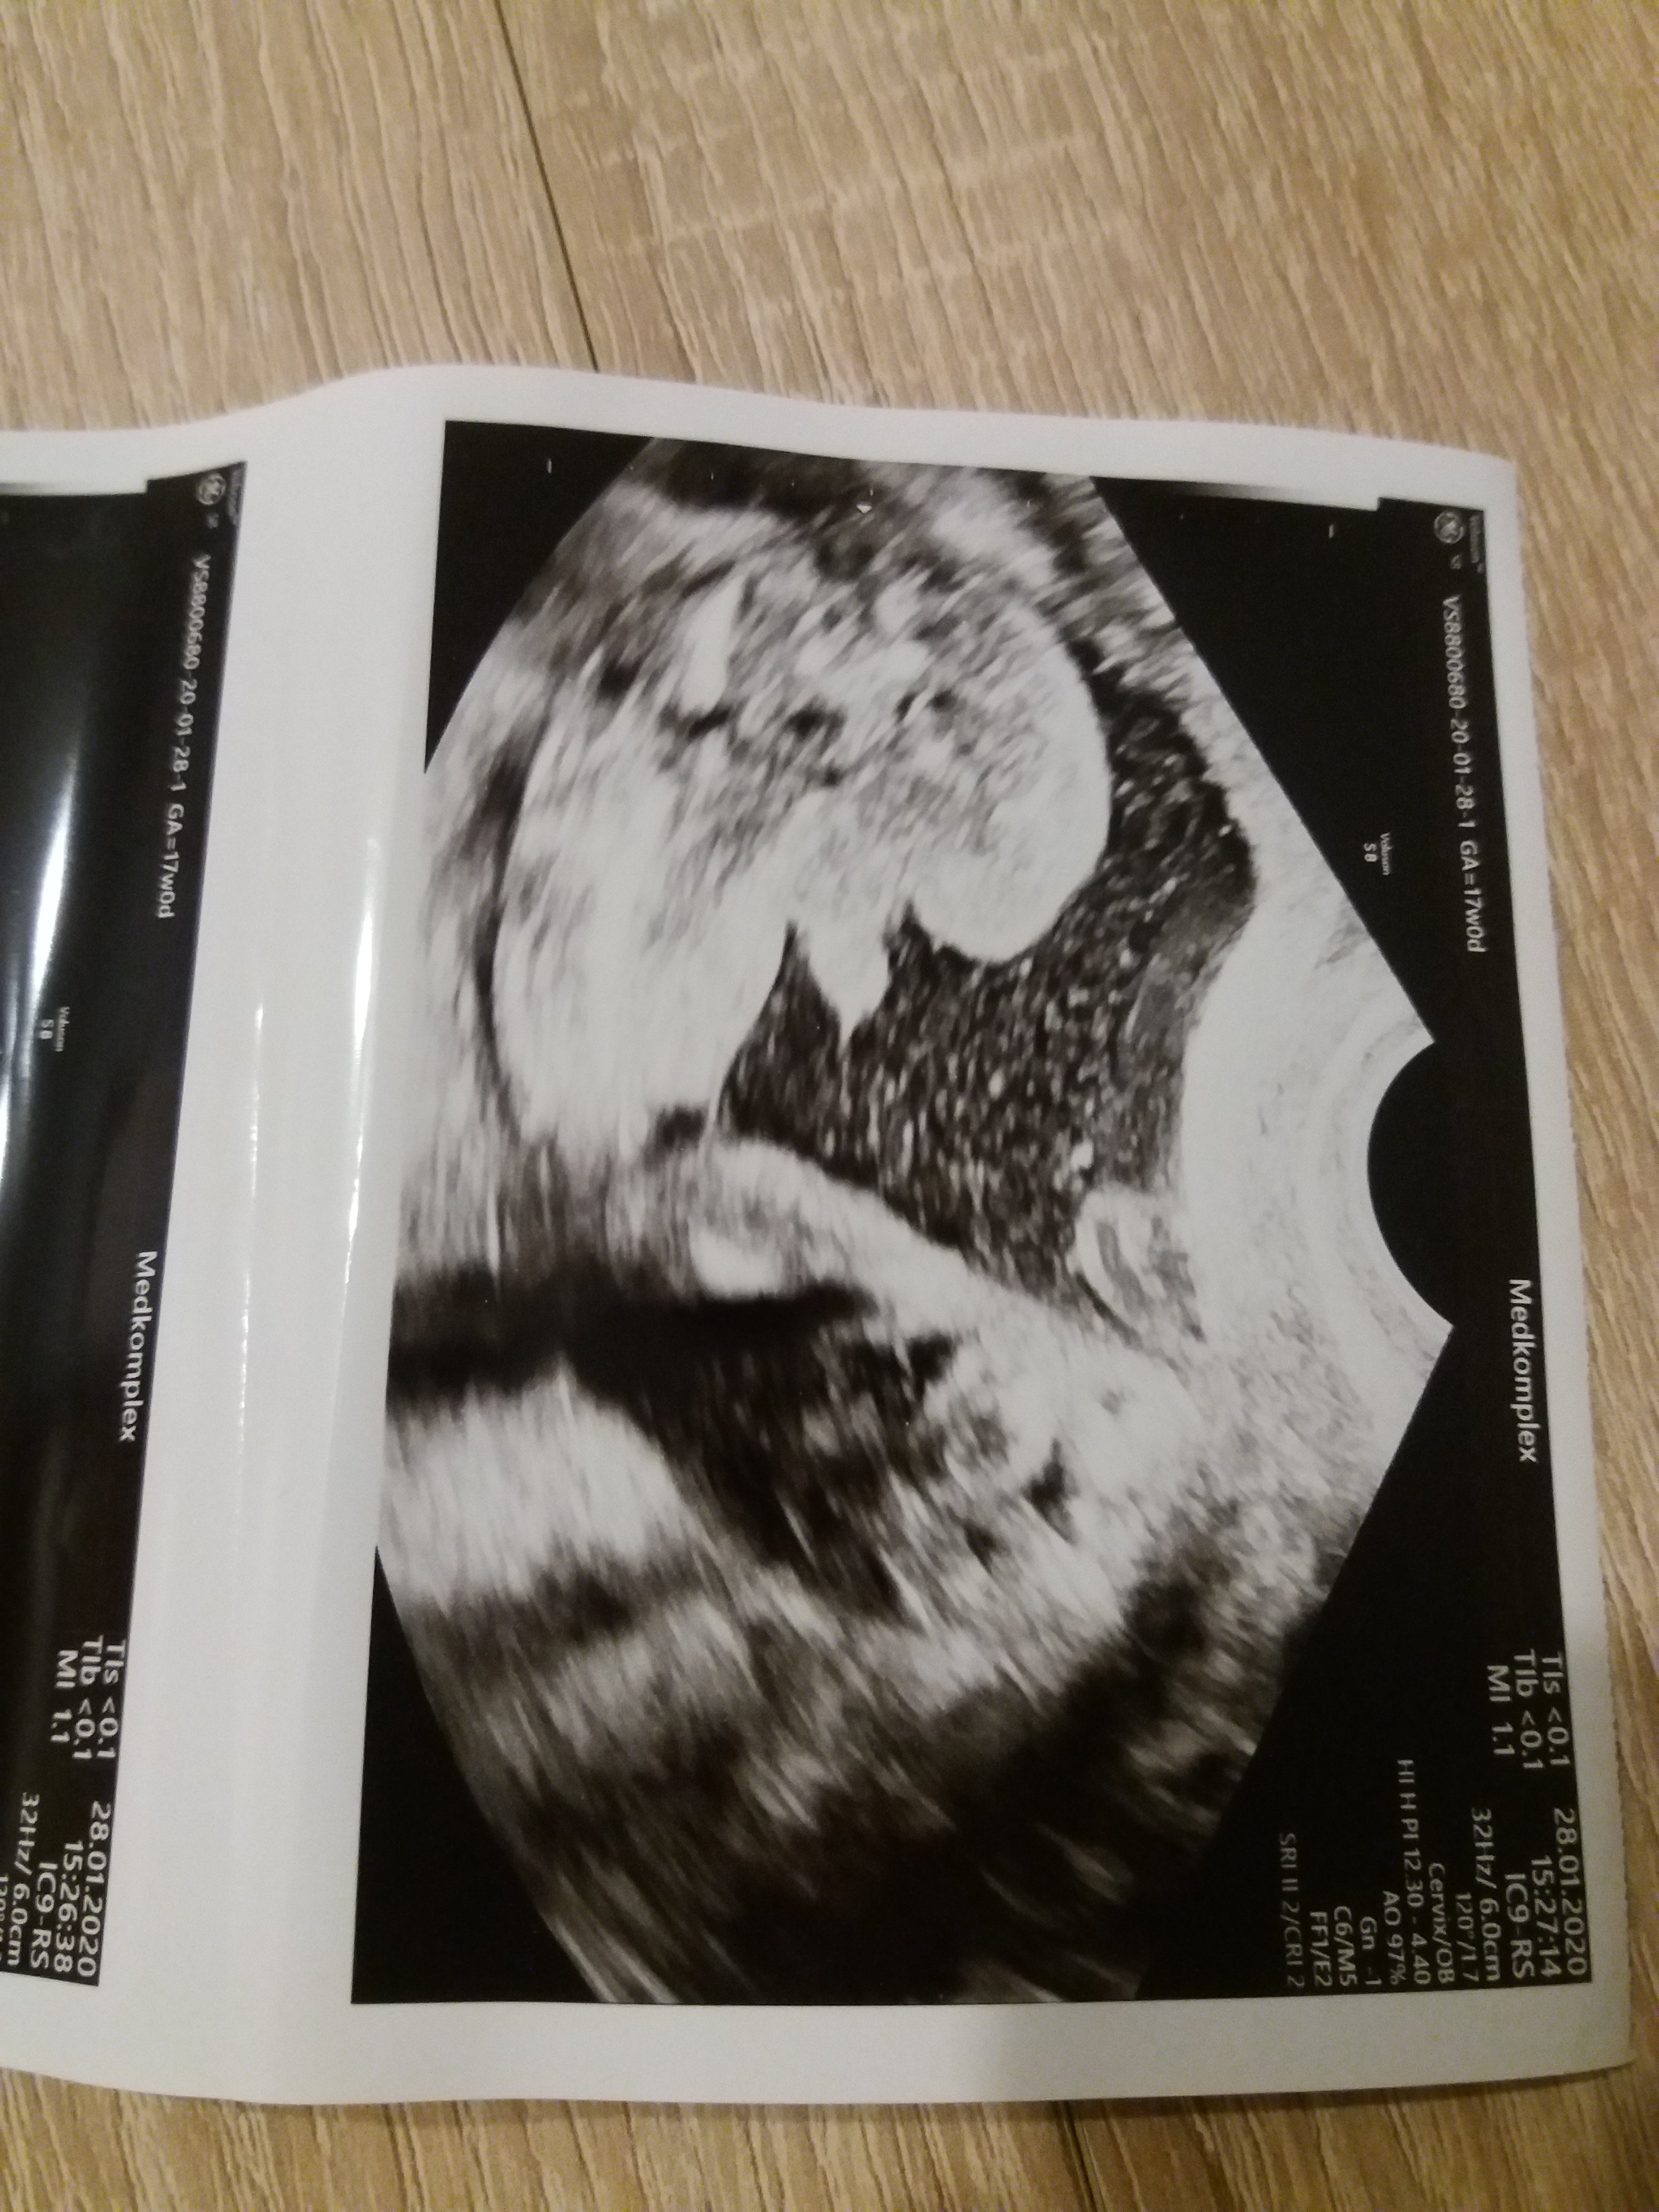

Czesc. Moja zona jest w 17tc ciazy, wczoraj wrocila od ginekologa ktory stwierdzil ze bedzie chlopak. Na zdieciu widac podobno siusiaka , czy istnieje prawdopodobienstwo ze lekarz sie myli ? Zastanawia mnie czemu na zdieciu nie widac moszny. Pozdrawiam przyszle mamy

Ewidentnie chłopak :)

Masz tu zdjęcie mojego dla porównania